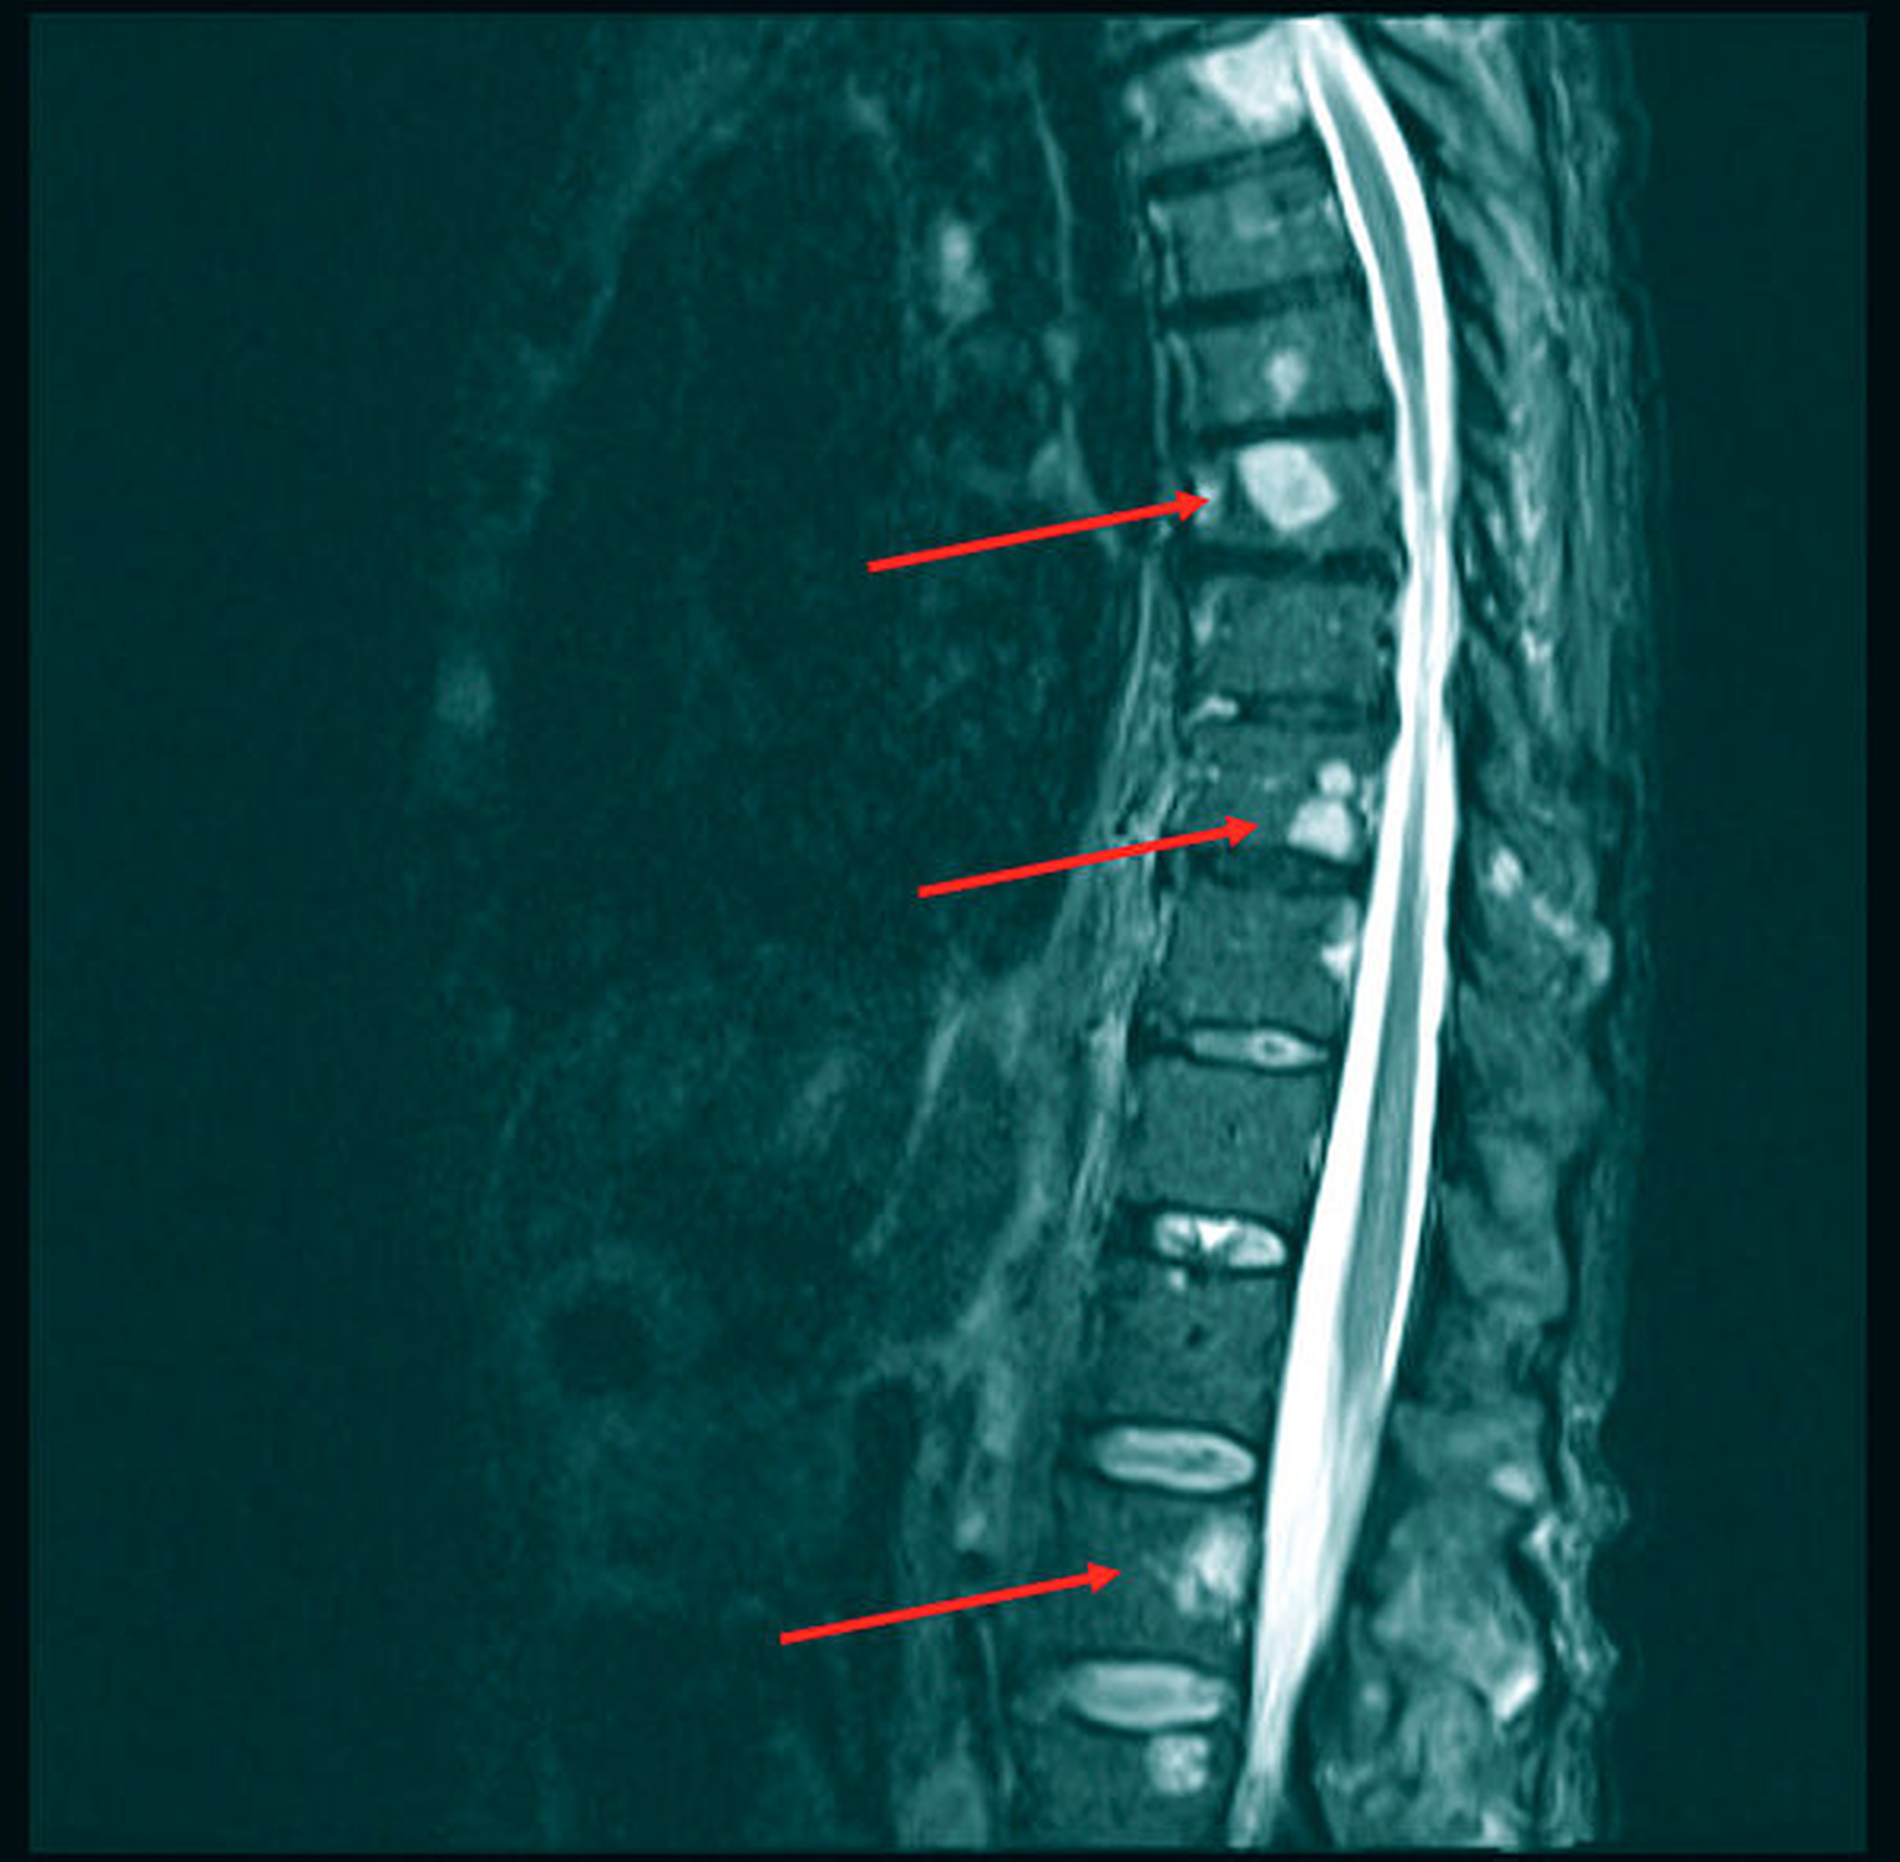

Im Rahmen der Leitlinien-gerechten Nachsorge mit jährlicher CT-Kontrolle und klinisch-sonografischer Inspektion alle ein bis drei Monate im ersten Jahr ergab sich kein Anhalt für das Vorliegen eines Lokalrezidivs, eines Zweitmalignoms oder einer lokalen Lymphknotenmetastasierung. Im Juli 2020 wurde die Patientin dann mit Atemnot und thorakalen Schmerzen sowie einer Belastungsdyspnoe notfallmäßig vorstellig. Der Befundbericht eines kürzlich extern bei Rückenschmerzen angefertigten MRTs beschrieb die Zeichen einer ossären Wirbelkörpermetastasierung sowie einen beidseitigen Pleuraerguss (Abbildung 2).

Trotz Radio- und Chemotherapie in den Jahren 2019 und 2020 imponierten in den nachfolgenden CT- und MRT-Untersuchungen weitere Metastasen in der Leber, in der rechten Niere sowie im Achsenskelett und in der Schädelkalotte als disseminierte osteolytische Knochenmetastasen (Abbildung 3). Weitere Therapiemaßnahmen lehnte die Patientin ab; sie wurde auf eigenen Wunsch in die Häuslichkeit entlassen.